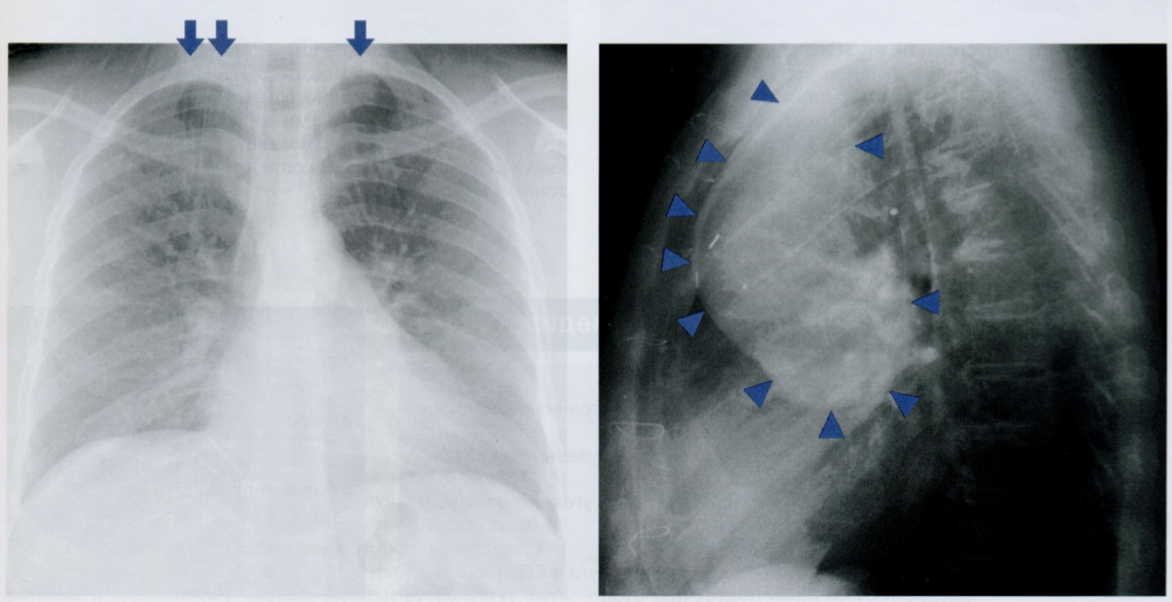

Внимательно рассмотрите снимок с метастазами (стрелочка) и плевральным выпотом (звездочка). Это случай поздней стадии рака. Оцените позвонки в БП.

Попытайтесь определить тип метастаза и предопложить источник первичной опухоли.

На снимке представлен пример распространенного метастазирования в кости при раке предстательной железы в далеко зашедшей стадии.

Мы видим генерализованное диффузное увеличение рентгеновской плотности костей. Посмотрим на боковую проекцию, оценим позвонки. Такой позвоночник называют “с позвонками из слоновой кости”.

Стрелочкой отмечен изолированный очаг остеолиза. Такой смешанный литико-бластический тип метастазирования характерен для рака предстательной железы, молочной железы и опухолей ЖКТ. Звездочкой отмечен плевральный выпот.